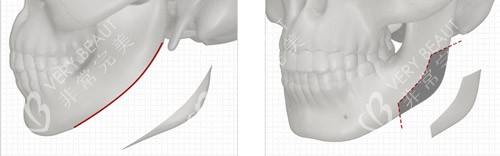

双鄂手术是Faceline的特色项目之一,在国内被称为“正颌手术”。

李真秀是将双鄂手术从大学功能医院引申到整容手术的头一人。

在理论轮廓术上,双颚与牙科联合坐诊是很有必要的,而Faceline在这方面做得十分出色。

在进行双鄂或面部轮廓手术时,医院会考虑十种面部情况。

首先设定手术后的变化目标,然后逆转计算骨移动和删除量、手术范围和角度。

这种科学、更准一些的手术计划制定方式,能更好地满足求美者的需求,实现自然美观的整形结果。